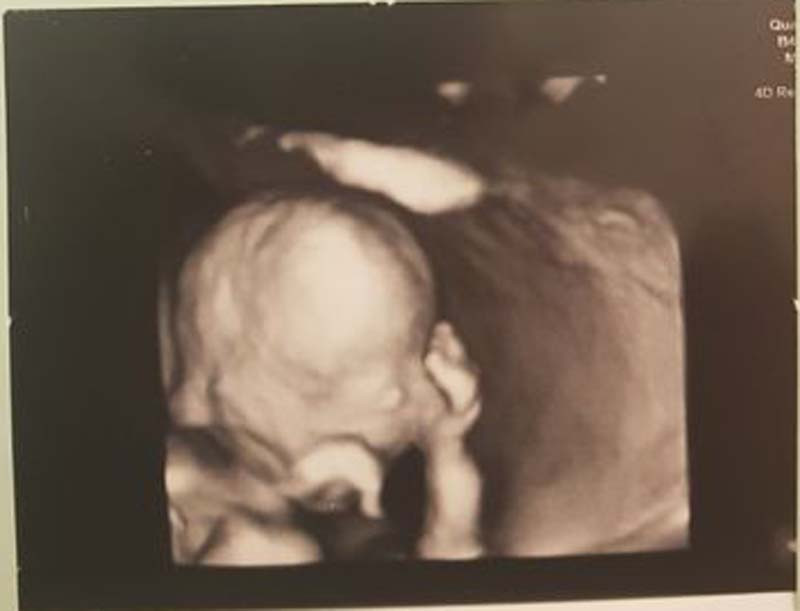

Chị My cho hay, khi mang thai lần 2 được 4,5 tháng chị có đi siêu âm và hỏi bác sĩ về giới tính em bé thì được tiết lộ là bé trai. Chị hỏi đi hỏi lại 3 lần bác sĩ vẫn khẳng định là bé trai. Sau đó, chị vẫn đi siêu âm định kỳ hàng tháng nhưng mặc định là đang bầu bé trai nên cũng không hỏi thêm bác sĩ về giới tính của bé.

Đến khi em bé được 7 tháng tuổi, chị đi siêu âm và hỏi lại bác sĩ một lần nữa về giới tính của bé thì bác sĩ vẫn nói là con trai. Lúc này, chị My chắc nịch là sắp đón một hoàng tử nên hai vợ chồng đi mua sắm đồ đạc cho con, tất cả mọi thứ đều "xanh lè xanh lẹt".

Trước khi mổ, chị My được đưa đi siêu âm để kiểm tra tình hình của thai nhi, bác sĩ vẫn khẳng định là bé trai. Vậy nhưng sau khi mổ xong, em bé chào đời còn chưa cắt rốn, bác sĩ liền nói với chị My em bé là con gái, nặng 3,4kg.

Đến bây giờ chị My vẫn không hiểu sao bác sĩ lại siêu âm nhầm cho chị như vậy, mà nhầm đến tận trước khi đẻ mới thật là hài hước.